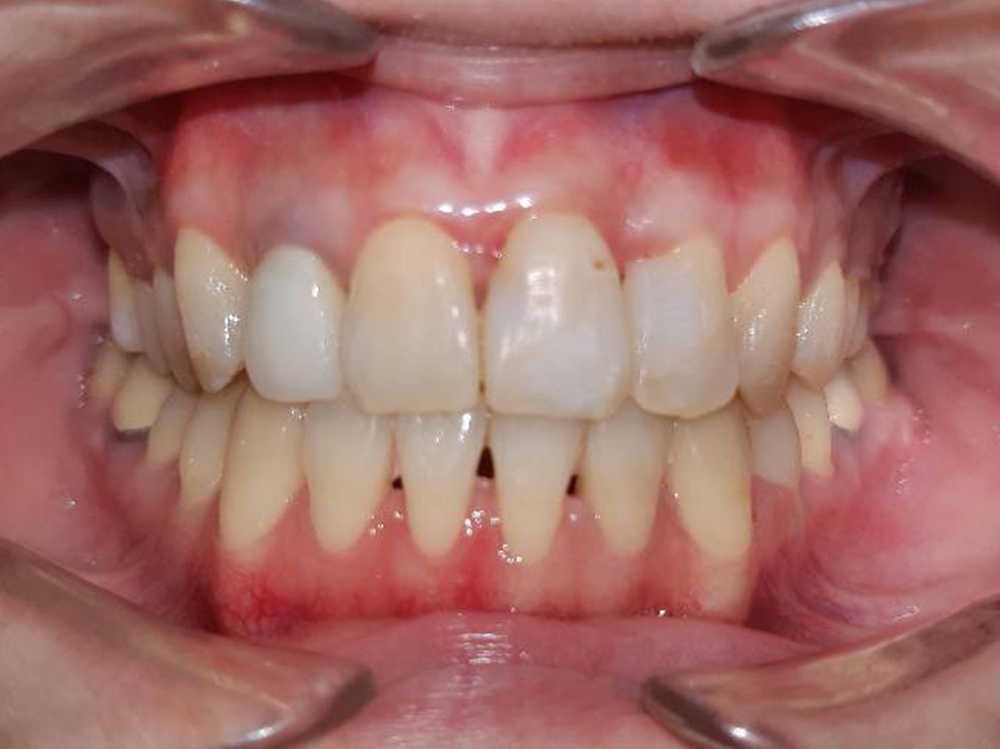

案例:不開刀齒性戽斗前後比較